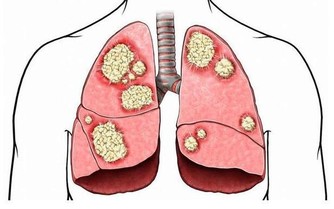

腎小球腎炎、糖尿病腎病、高血壓腎病、痛風腎、多囊腎等都被統稱為“慢性腎病”。當腎臟受損時,患者體內的毒素難以被過濾,逐漸會引起上述症狀。而這類疾病通常無法根治,唯有找到致病原因、確定疾病類型,才能通過相應的治療控制病情,緩解不適感。常見的檢查方法包括血液檢查、放射性核素腎掃描、活體組織檢查等。